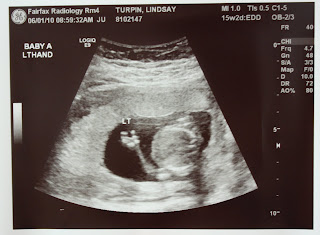

BabyA Waving Hello: